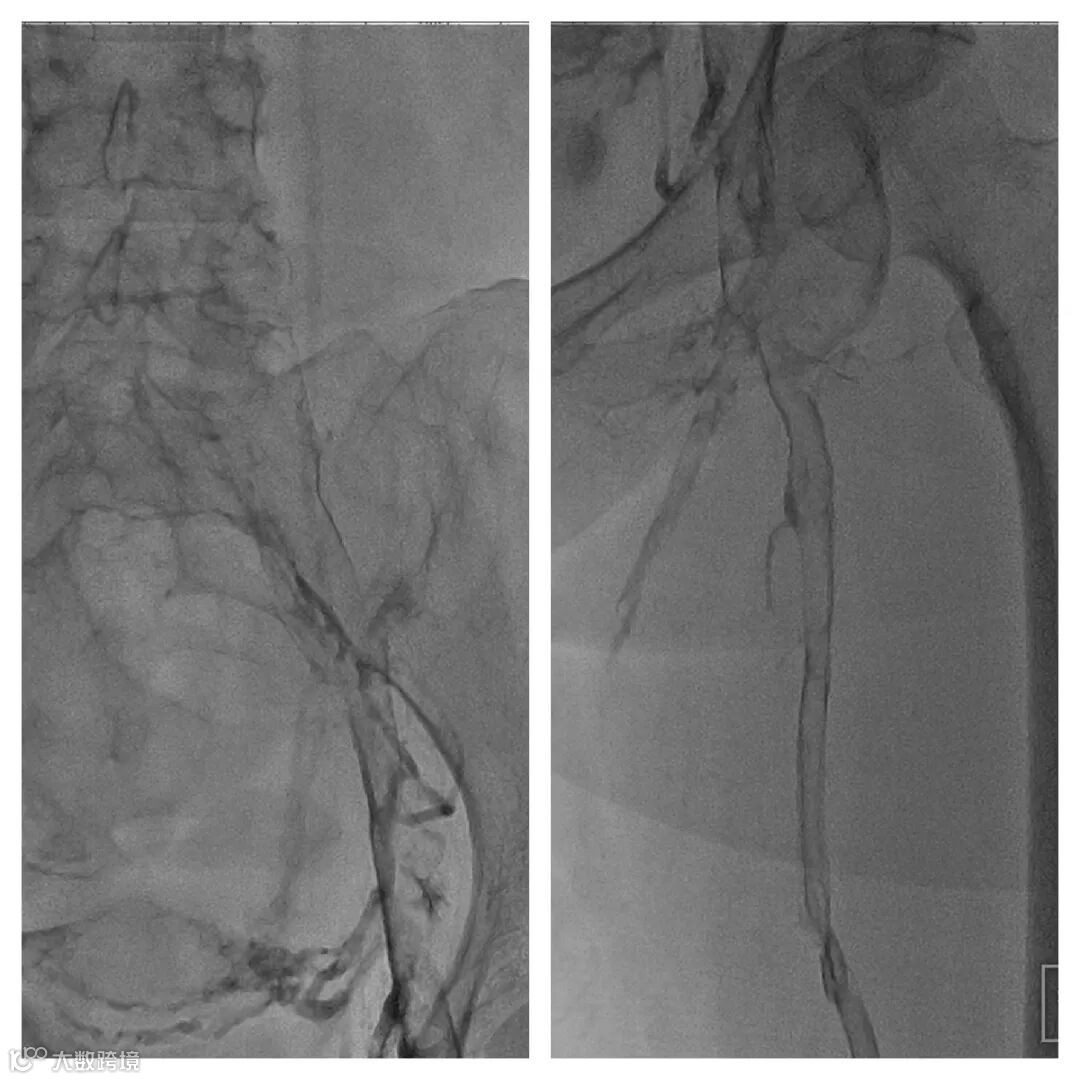

4. 送入腾复Tendfast®外周静脉取栓支架,左股静脉拉栓1次,造影显示:左股静脉血流通畅。

5. 左髂静脉血栓负荷较重,通过左髂总静脉后,给予6mm*150mm球囊扩张。

6. 引入Tendfast®外周静脉取栓支架,从左侧髂静脉拉栓2次,造影显示血流恢复通畅。